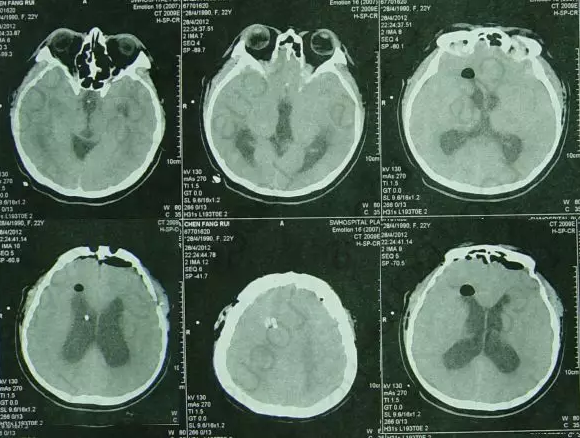

内镜造瘘术后第4天即脑室外引流拔除后第2天即2012年5月2日,腰穿提示颅内压高达400mmH20,查头CT:三脑室又扩大(图-4),查头MRI:小脑扁桃体轻微下疝(图-5),医生考虑三脑室再次扩大跟小脑扁桃体下疝有关,给予腰大池引流相关治疗。

图-4:2012年5月2日头CT

图-5:2012年5月2日头MRI

查头颅CT:脑室扩张,左侧侧脑室外引流术后状态(图-6)。

图-6:2012年5月4日头CT